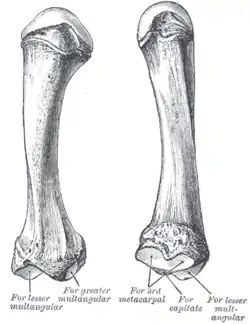

Micro-radiography of 8 weeks human embryo hand Second metacarpal bone

Second metacarpal bone Third metacarpal bone